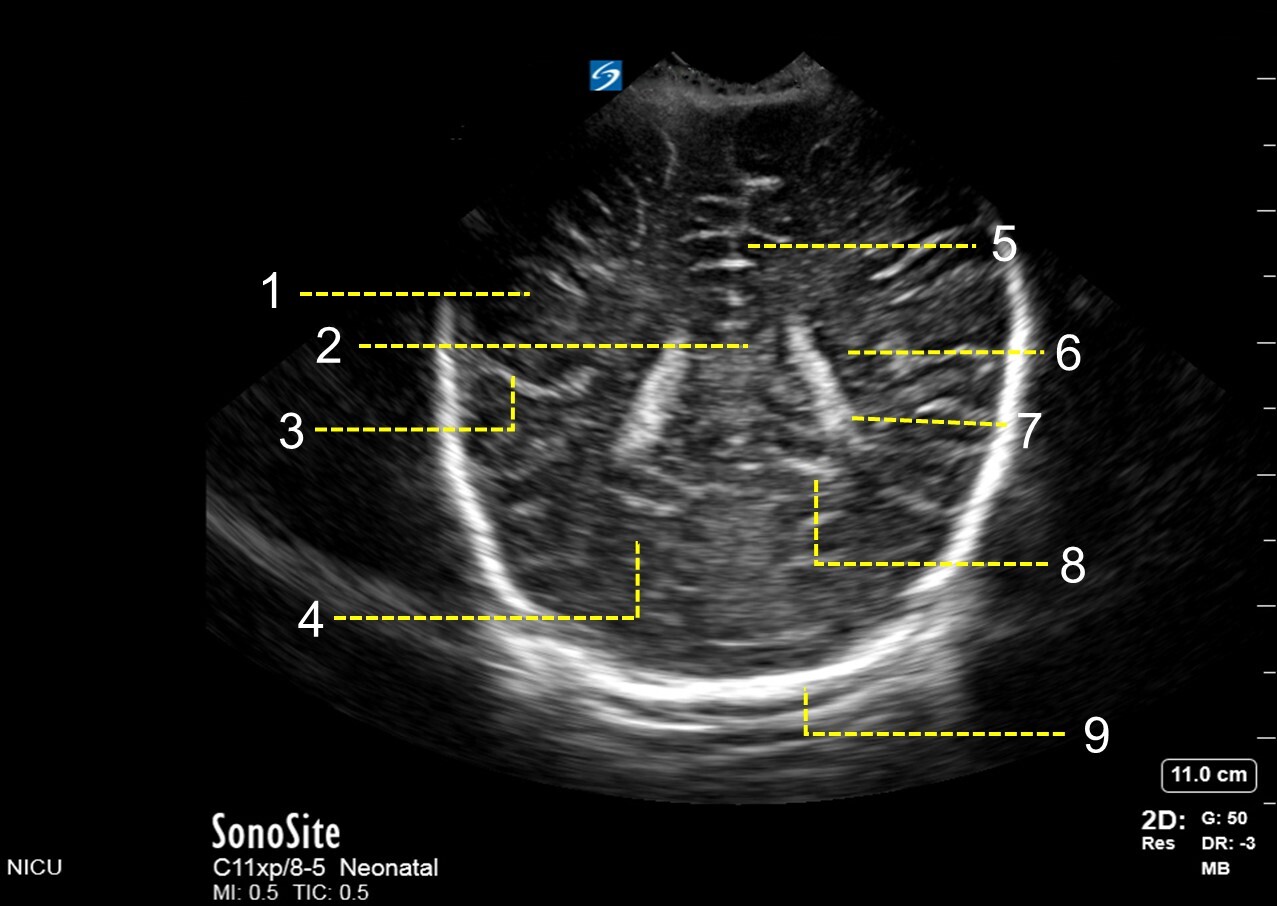

1. Parietal Lobe

2. Corpus Callosum

3. Sylvain Fissure

4. Occipital Lobe

5. Inter Hemispheric Fissure

6. Body of Lateral Ventricle

7. Choroid Plexus

8. Calcarine Fissure

9. Skull